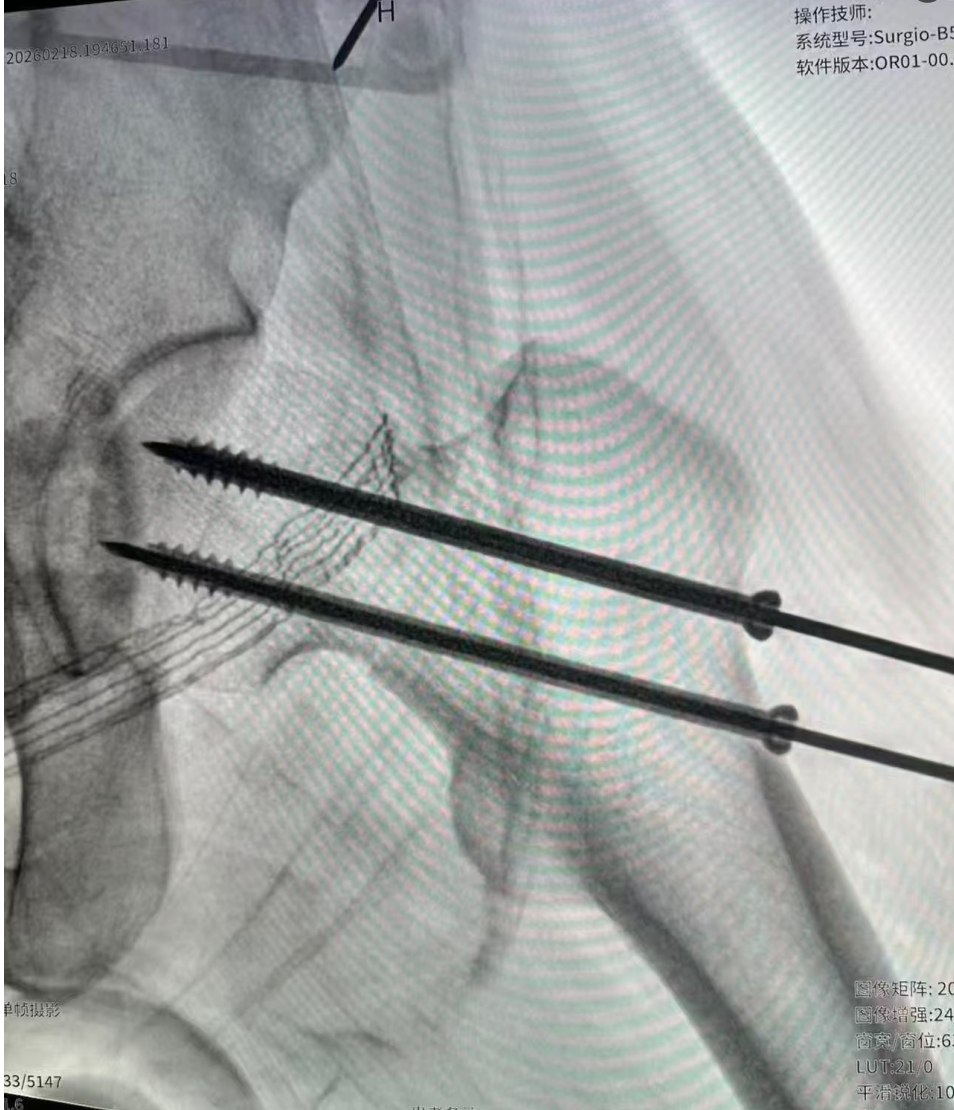

当晚 9 点,手术顺利开始。

在骨科手术导航机器人的辅助下,团队精准复位骨折端,置入内固定装置,手术过程一气呵成,没有出现任何并发症。